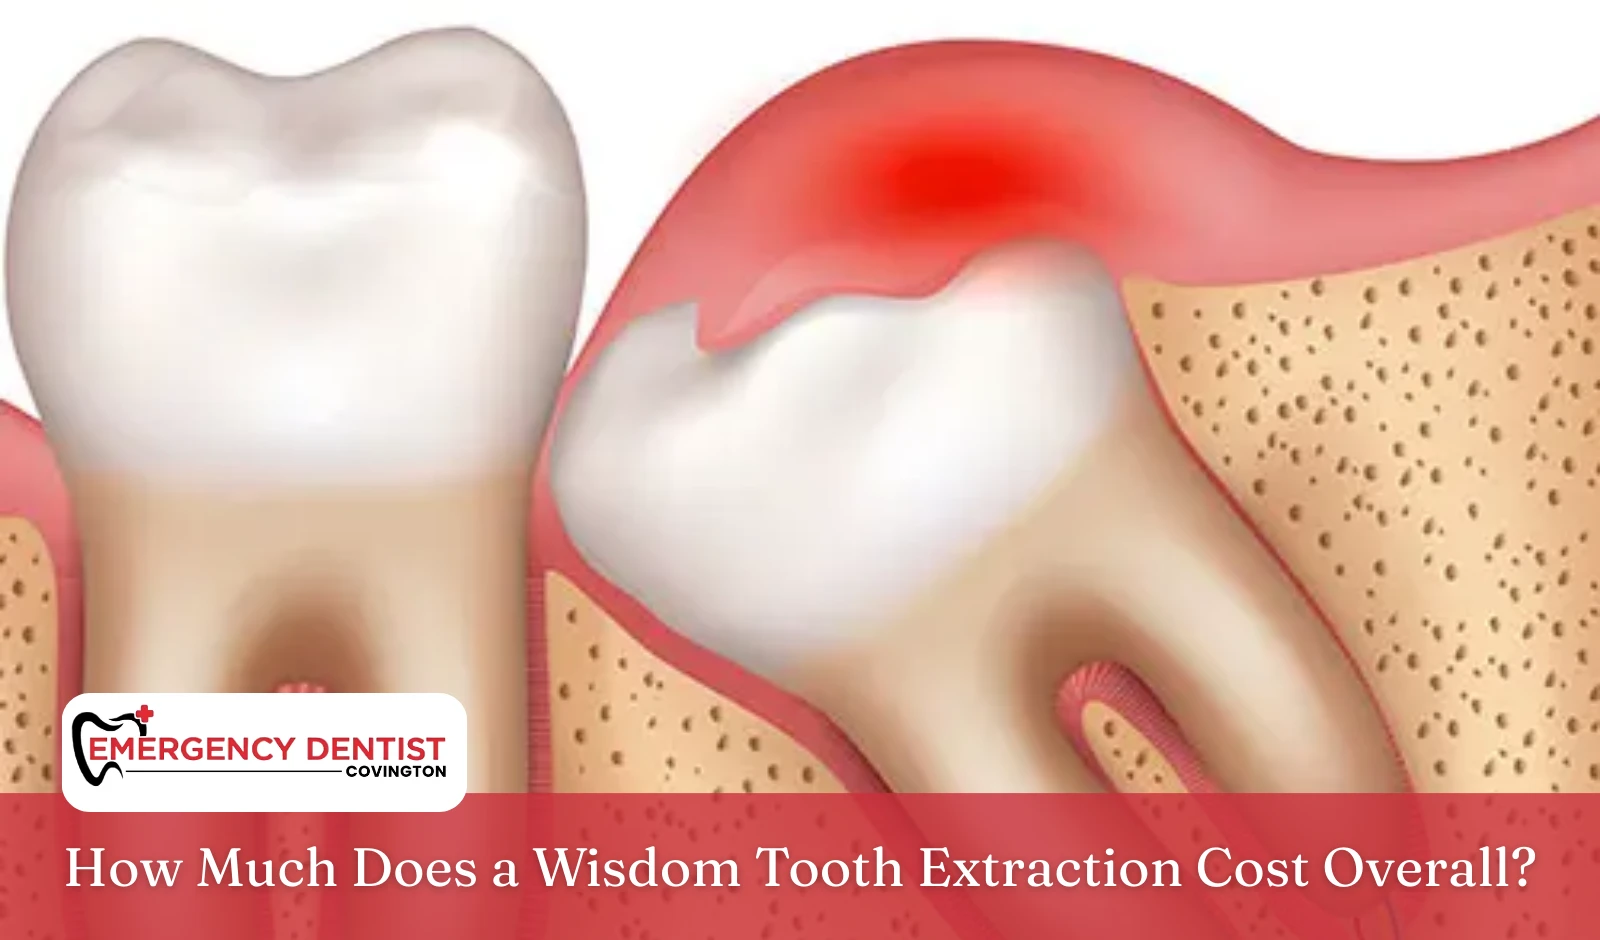

What Happens During Wisdom Teeth Extraction

Wisdom teeth are the last molars to grow in. Many people do not have enough space in their mouths for them to develop properly. During an exam, a dentist evaluates:

- Tooth position

- Whether the tooth is fully erupted

- Signs of infection or crowding

- Bone and gum health

Wisdom teeth extraction is often recommended to protect long-term oral health. When left untreated, these teeth can trap bacteria and increase the risk of swelling, decay, and damage to nearby teeth.

A surgical extraction is necessary when the tooth is partially erupted, broken, or located beneath the gums. This is common with an impacted wisdom tooth.

How an Impacted Wisdom Tooth Affects Cost

An impacted wisdom tooth does not fully come through the gums. It may grow sideways or push against neighboring teeth. These situations often require oral surgery.